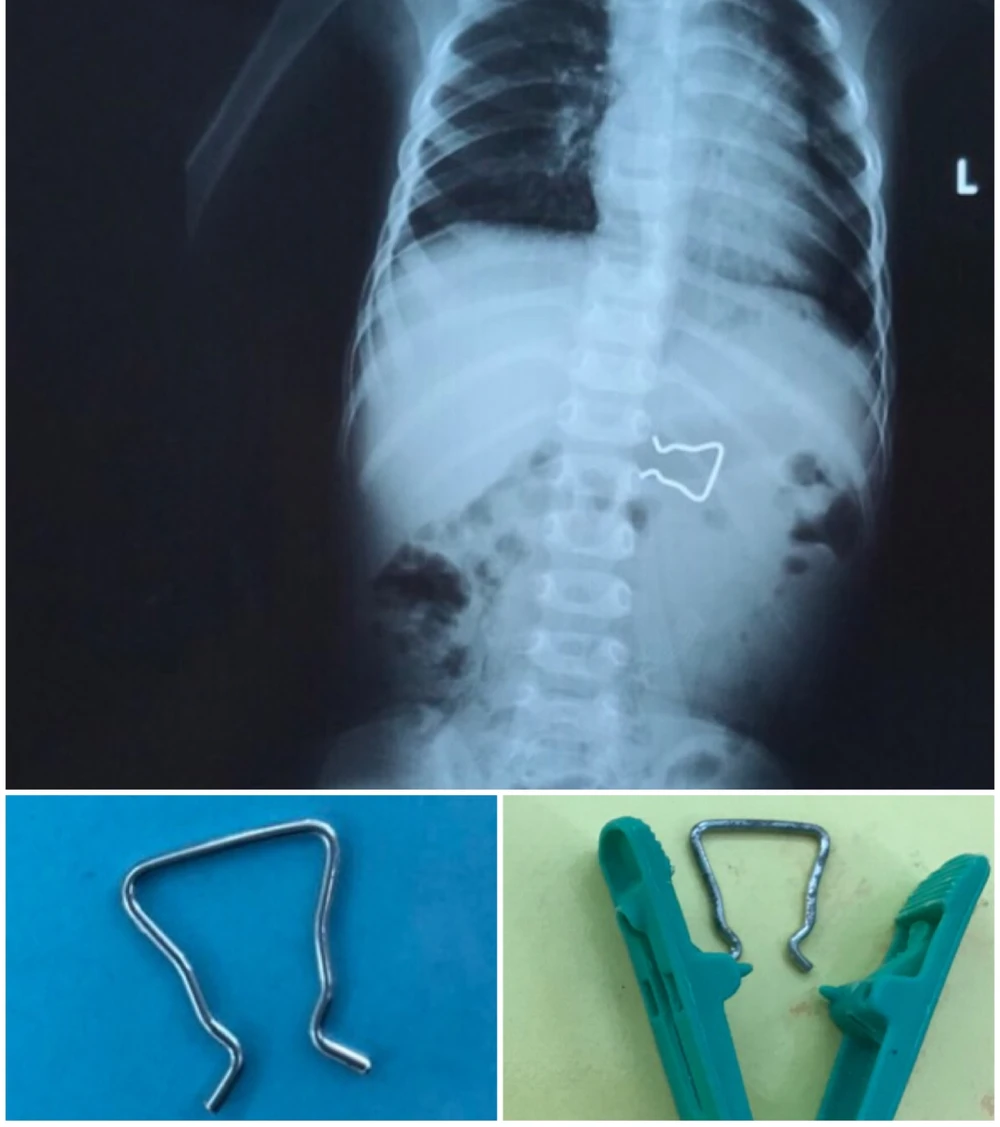

Hình ảnh sau khi chụp X-quang cho thấy dị vật là chiếc móc sắt dùng để cố định trong kẹp quần áo.

Hình ảnh chụp X-quang và dị vật là móc sắt cố định trong kẹp áo. Ảnh: BV

Khi tiếp nhận bệnh nhi, êkíp nội soi tiêu hóa nhận định đây là trường hợp khó do hình dáng dị vật có hai cạnh sắc nhọn, kích thước lớn, khi gắp dị vật có thể gây tổn thương nhiều hơn niêm mạc đường tiêu hóa.

Cạnh đó, việc gắp dị vật cần phải được tiến hành ngay trước khi dị vật di chuyển sâu hơn, gây biến chứng thủng ruột. Êkíp đã nhanh chóng liên lạc và phối hợp cùng đồng nghiệp nội soi của BV Chợ Rẫy để thực hiện ca này.

Với kỹ thuật nội soi khéo léo, đồng thời dùng các dụng cụ có thể che chắn được cạnh sắc nhọn của dị vật, tránh gây trầy xước thêm đường tiêu hóa, dị vật đã được lấy ra một cách an toàn.